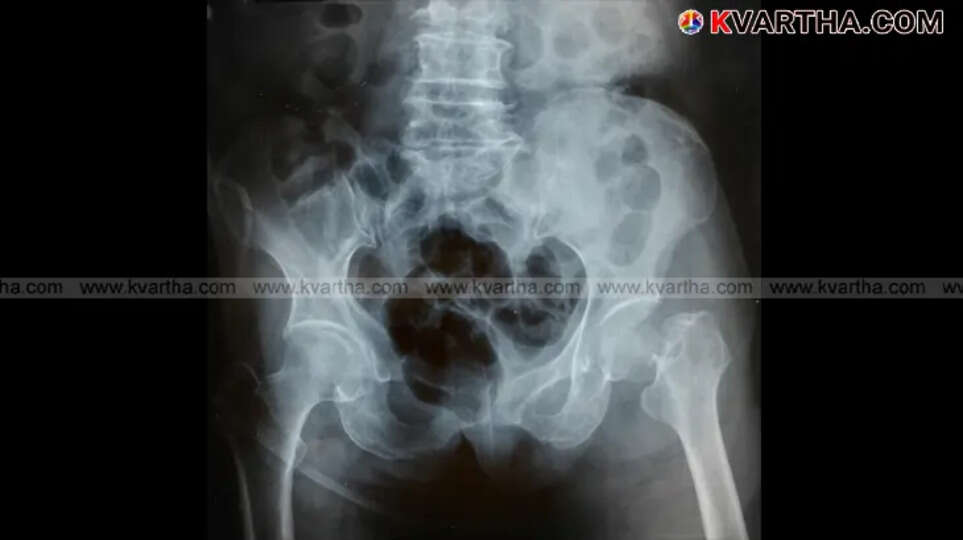

ഓസ്റ്റിയോപൊറോസിസ് നിർണ്ണയിക്കുന്നതിനുള്ള ഏറ്റവും നല്ല മാർഗ്ഗം ഡ്യുവൽ എനർജി എക്സ്-റേ അബ്സോർപ്റ്റോമെട്രി (DXA) ആണ്. ഇത് എല്ലുകളുടെ സാന്ദ്രത കൃത്യമായി അളക്കുന്നു. ശരിയായ ജീവിതശൈലി മാറ്റങ്ങളും പതിവായ വൈദ്യപരിശോധനയും വഴി എല്ലുകളെ സംരക്ഷിക്കുകയും ജീവിതകാലം മുഴുവൻ ചലനാത്മകതയും സ്വാതന്ത്ര്യവും നിലനിർത്തുകയും ചെയ്യാം.